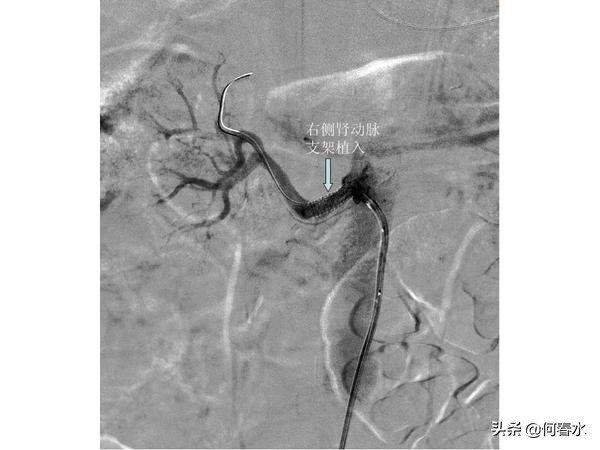

患者至今随访5年,支架通畅,头晕等脑缺血症状完全消失。但是春节后再次出现头晕不适,在职工医院检查发现右侧颈动脉重度狭窄,右侧颅内梗塞病灶,左侧颅内未有梗塞病灶。入住我科后,造影检查发现:右侧颈动脉重度狭窄伴有溃疡形成,左侧颈动脉支架通畅,右侧肾动脉重度狭窄。

(3)血管健康管理的重要性:患者有糖尿病、高血压、吸烟,5年来血管病变不断发展,直至累及右侧颈动脉和右侧肾动脉,面临再次脑中风及右肾功能丢失的风险,右侧颈动脉支架及右侧肾动脉支架避免了风险的发生,但是患者必须戒烟及严格控制血压,血糖,以防血管病变累及更多的血管;